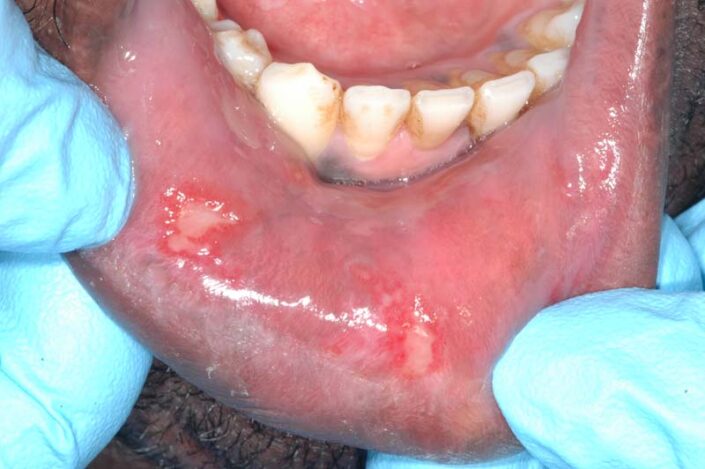

La si distingue facilmente dalla stomatite aftosa poichè interessa la quasi interezza della bocca associandosi a febbre fino a 40 gradi, nausea, gonfiore delle gengive brividi cefalee linfonidi ingrossati dolore e bruciore molto più forti e maggior numero di lesioni (vescicole a grappolo o lesioni tondeggianti di maggior dimensione contenenti un liquido sieroso limpido che una volte rotte portano ad ulcerazioni superficiali)sia sulla lingua sia sulla gengiva sia sul palato sulle labbra e sulla mucosa delle guance